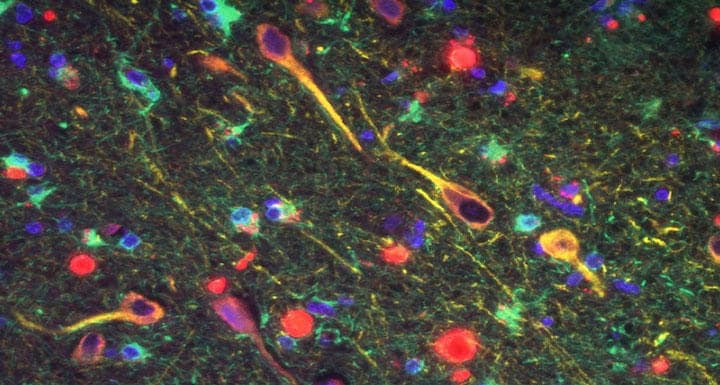

アルツハイマー病(アルツハイマー型認知症)」は、「アミロイドβ」といった特殊なタンパク質が脳内に蓄積し、正常な神経細胞を変化させることで、脳の働きを低下させたり、萎縮を進行させたりする脳疾患だ。

この研究結果によると、脳内には、ポルフィロモナス・ジンジバリス菌のほか、ポルフィロモナス・ジンジバリス菌が産生する毒性プロテアーゼ「ジンジパイン」も確認されており、そのレベルは、アルツハイマー病と関連のある「タウ・タンパク質」や「ユビキチン」との相関が認められている。

また、研究チームでは、マウスの口内にポルフィロモナス・ジンジバリス菌を感染させたところ、6週間後には脳内でポルフィロモナス・ジンジバリス菌が確認され、脳内の「アミロイドβ」も著しく増加した。